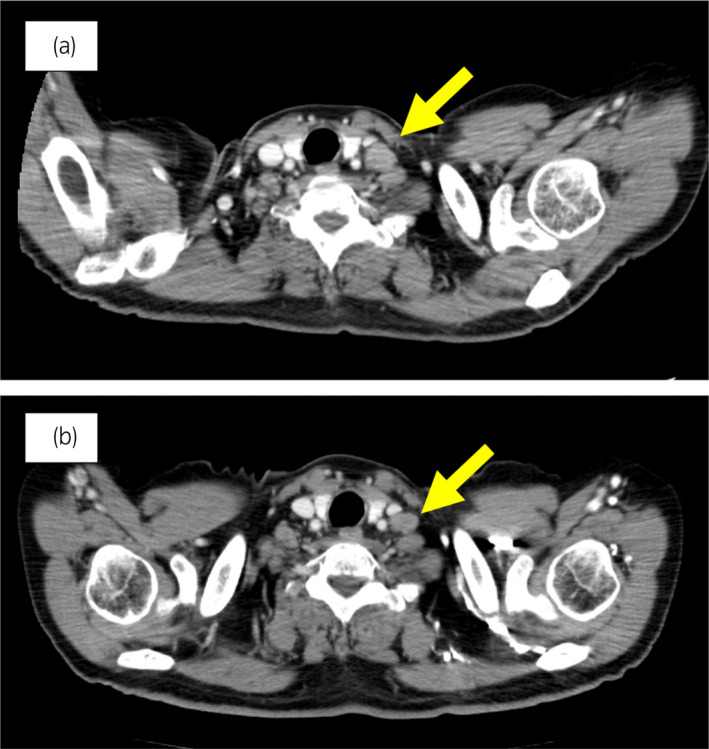

70 歲男性被診斷為轉(zhuǎn)移性 PC,cT3bN1M1b,Gleason 評(píng)分(GS)為 4 + 5 = 9,前列腺特異性抗原(PSA)水平為 40.8ng/ml,3 年前伴有胸椎轉(zhuǎn)移。 對(duì)前列腺進(jìn)行聯(lián)合雄激素阻斷 (CAB) 治療和質(zhì)子放射治療 (78.0Gy/39fr)。 PSA 水平降至 <0.01ng/ml,CAB 在 2.5 年后停止。 停止 CAB 五個(gè)月后,他出現(xiàn)背痛,PSA <0.01 ng/ml。 計(jì)算機(jī)斷層掃描 (CT) 掃描檢測(cè)到多處肝、骨和淋巴結(jié)轉(zhuǎn)移,神經(jīng)元特異性烯醇化酶 (NSE) 水平高達(dá) 171ng/ml(圖 1a)。 骨轉(zhuǎn)移活檢顯示神經(jīng)內(nèi)分泌前列腺癌 (NEPC) 的診斷(圖 2),患者被轉(zhuǎn)診至佳學(xué)基因合作醫(yī)院。 內(nèi)分泌腫瘤正確治療醫(yī)生用順鉑、依托泊苷和亮丙瑞林治療。 第三個(gè)療程后,轉(zhuǎn)移部位明顯縮?。▓D 1b)。 順鉑和依托泊苷治療 1 年,但患者因神經(jīng)病變要求停藥。 他開(kāi)始服用恩雜魯胺。 治療 3 個(gè)月后,患者出現(xiàn)背痛和左鎖骨下淋巴結(jié)腫大(圖 3a)。 肝轉(zhuǎn)移保持不變,順鉑治療后縮小。 通過(guò)腫瘤正確用藥850基因檢測(cè)證實(shí)了 BRCA2 突變。根據(jù)基因檢測(cè)結(jié)果,主治腫瘤科醫(yī)生給予了奧拉帕尼。 三個(gè)月后,背痛好轉(zhuǎn),淋巴結(jié)轉(zhuǎn)移縮小,確定為部分緩解(PR)(圖3b)。 肝轉(zhuǎn)移灶保持不變。

圖1:病例1.順鉑和依托泊苷三個(gè)療程前后的腹部CT圖像。 (a) 治療前和 (b) 治療后。

圖 3:案例 1. 開(kāi)始使用奧拉帕尼之前和之后 3個(gè)月的鎖骨下淋巴結(jié)轉(zhuǎn)移的 CT 圖像。 (a) 治療前和 (b) 奧拉帕尼治療后 3 個(gè)月。 黃色箭頭顯示轉(zhuǎn)移淋巴結(jié)。